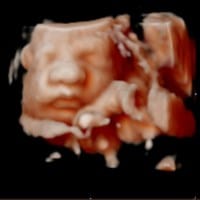

Aterrada... ¿Alguien qué tenga conocimiento en ecografías? Necesito aclarar mi duda :(

Me hice una ecografías 5d a las 31 semanas y sale la nariz del bebe muy demasiado ancha :( ¿Es normal por los movimientos? ¿Por el liquido? ¿Mucho zoom? Y los labios también muy gruesos... Quede aterrada porque no es normal tan ancha una nariz así...